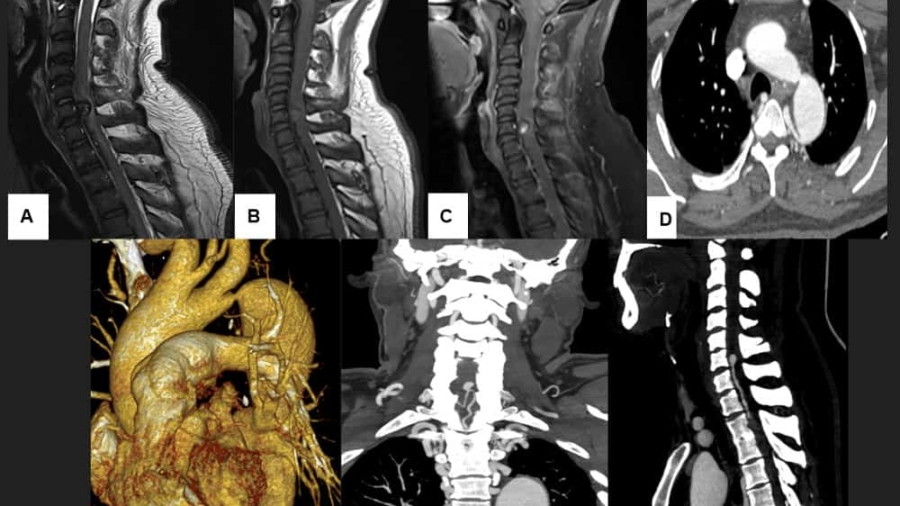

A 36 year old hypertensive male presented with gradually progressive weakness of bilateral upper and lower limb weakness since 1-2 months.